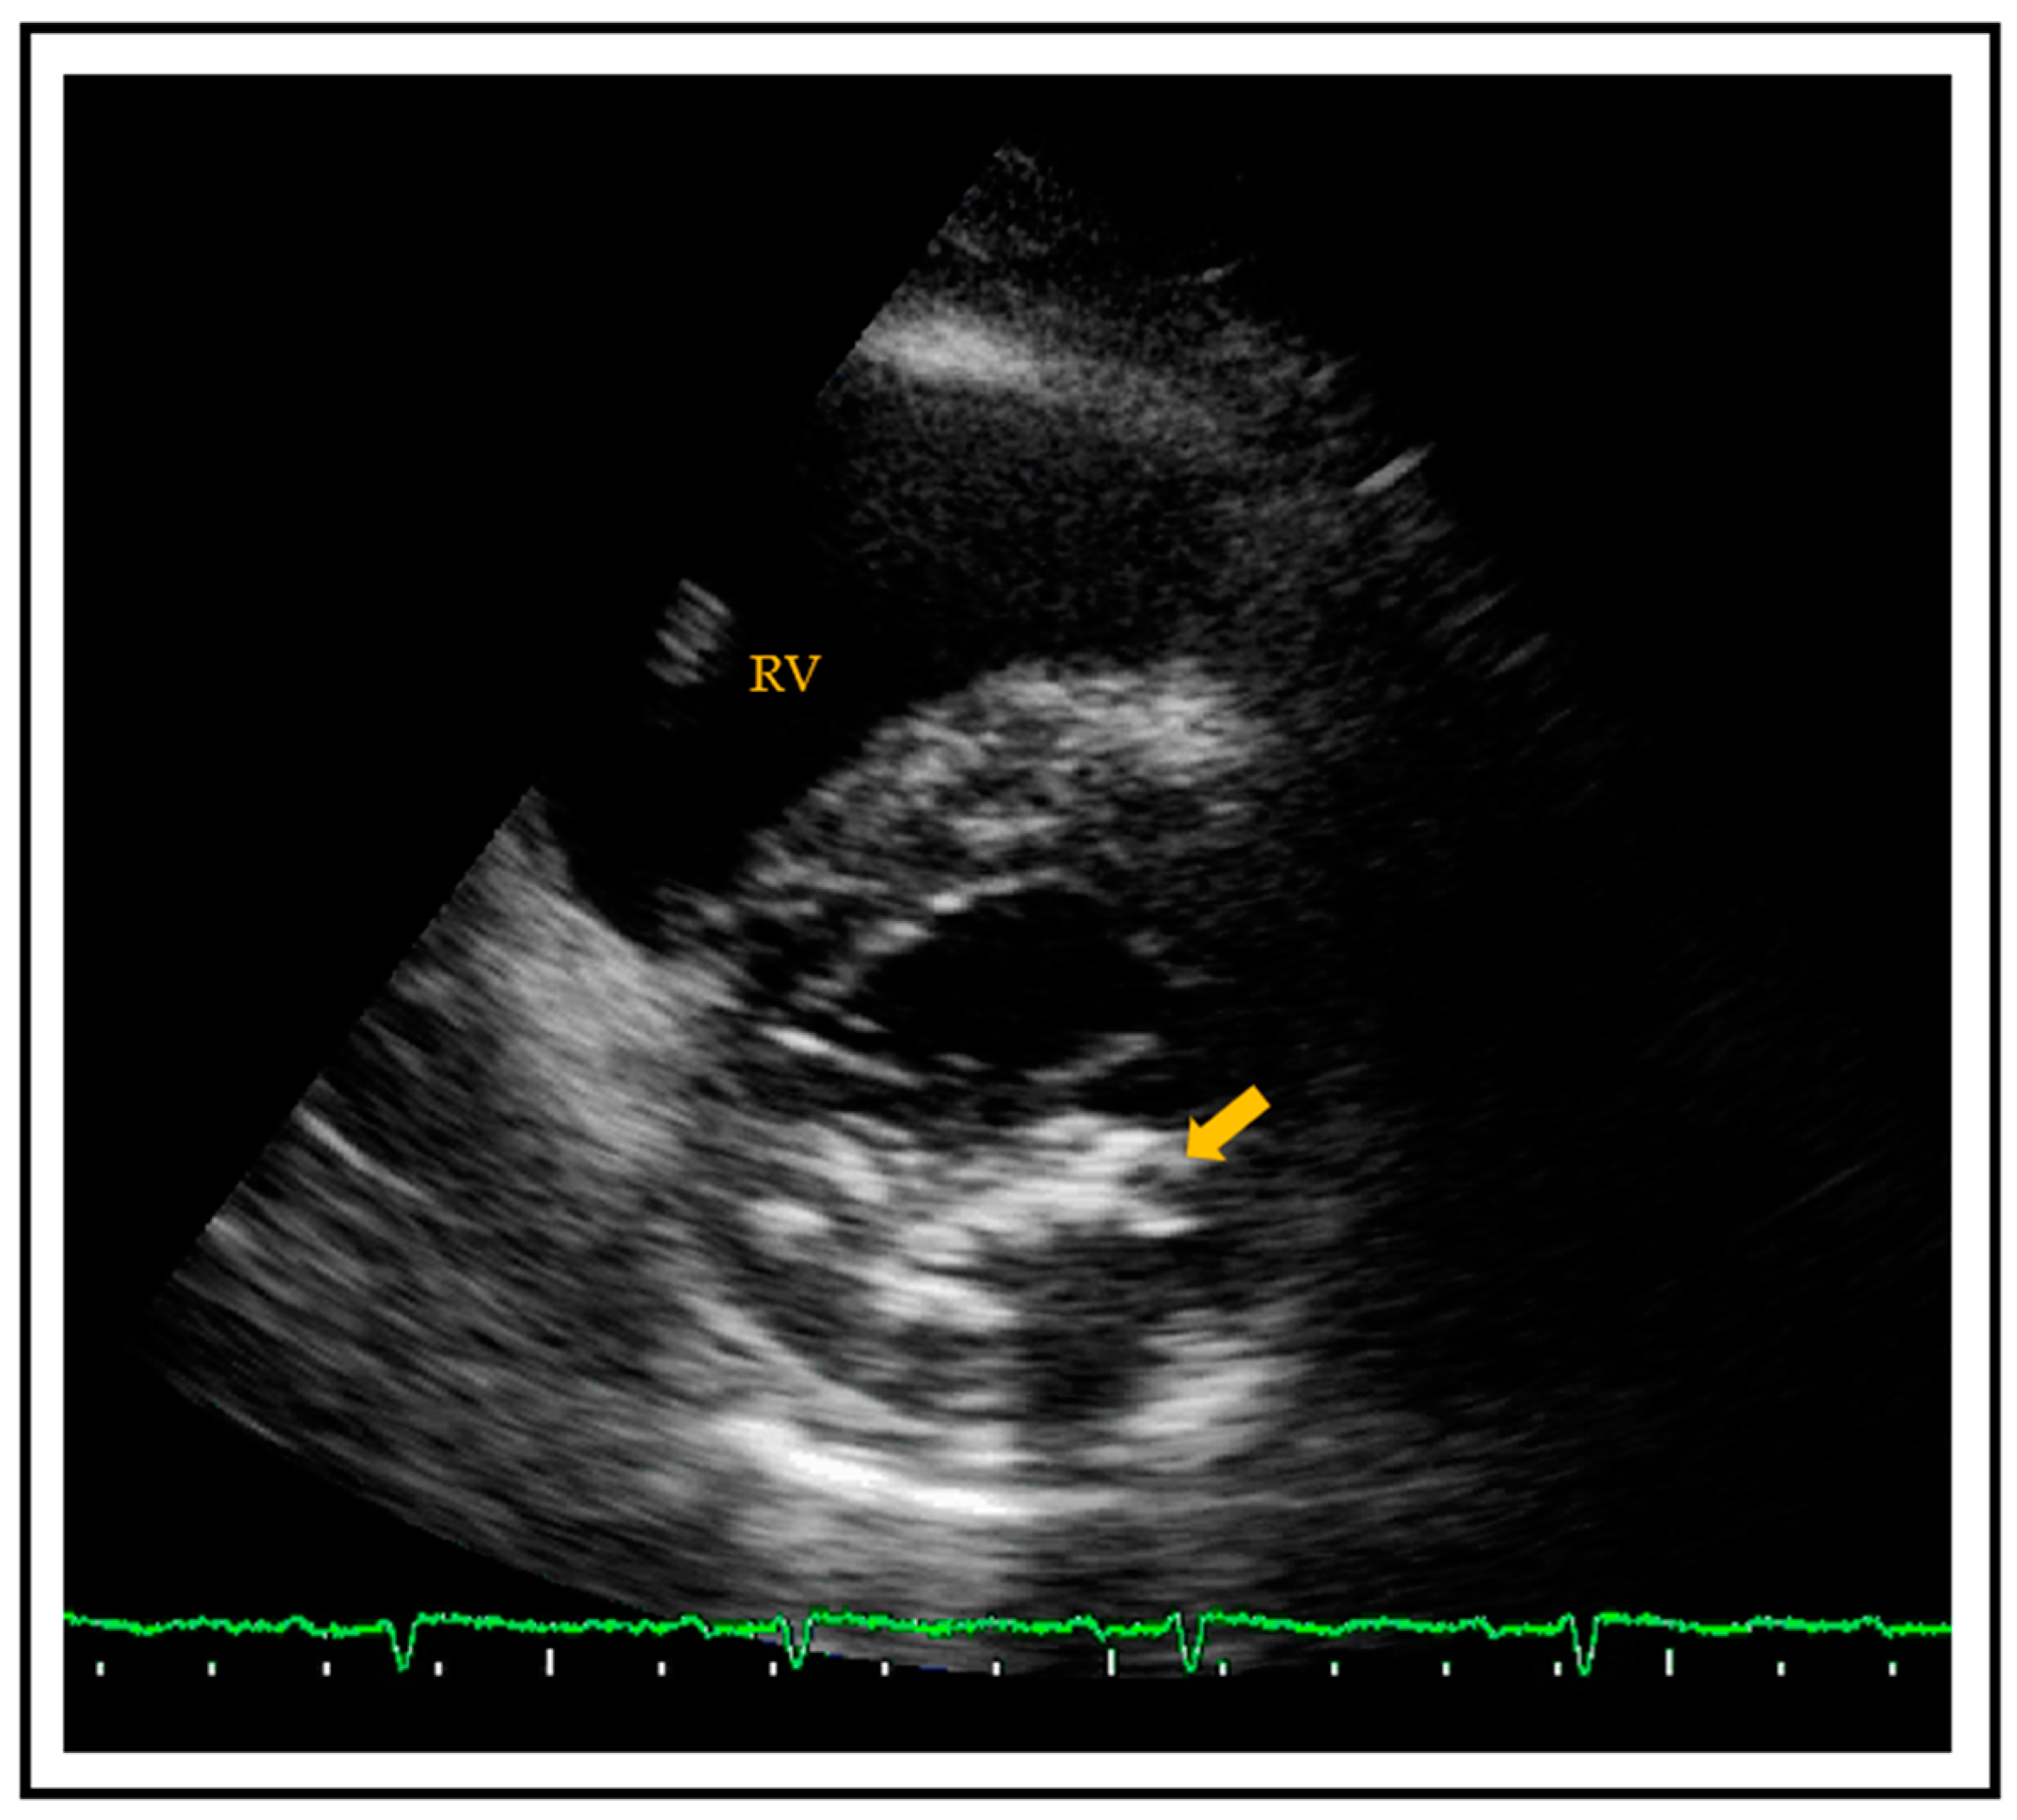

- Weissler-Snir, A.; Greenberg, G.; Shapira, Y.; Weisenberg, D.; Monakier, D.; Nevzorov, R.; Sagie, A.; Vaturi, M. Transoesophageal echocardiography of aortic atherosclerosis: The additive value of three-dimensional over two-dimensional imaging. Eur. Heart J. Cardiovasc. Imaging 2015. [Google Scholar] [CrossRef]